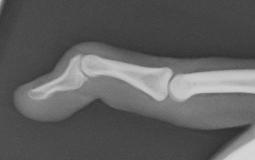

腱性槌指のスプリント固定の一例

末節骨変形治癒骨折の骨切術(左:術前・右:術後)